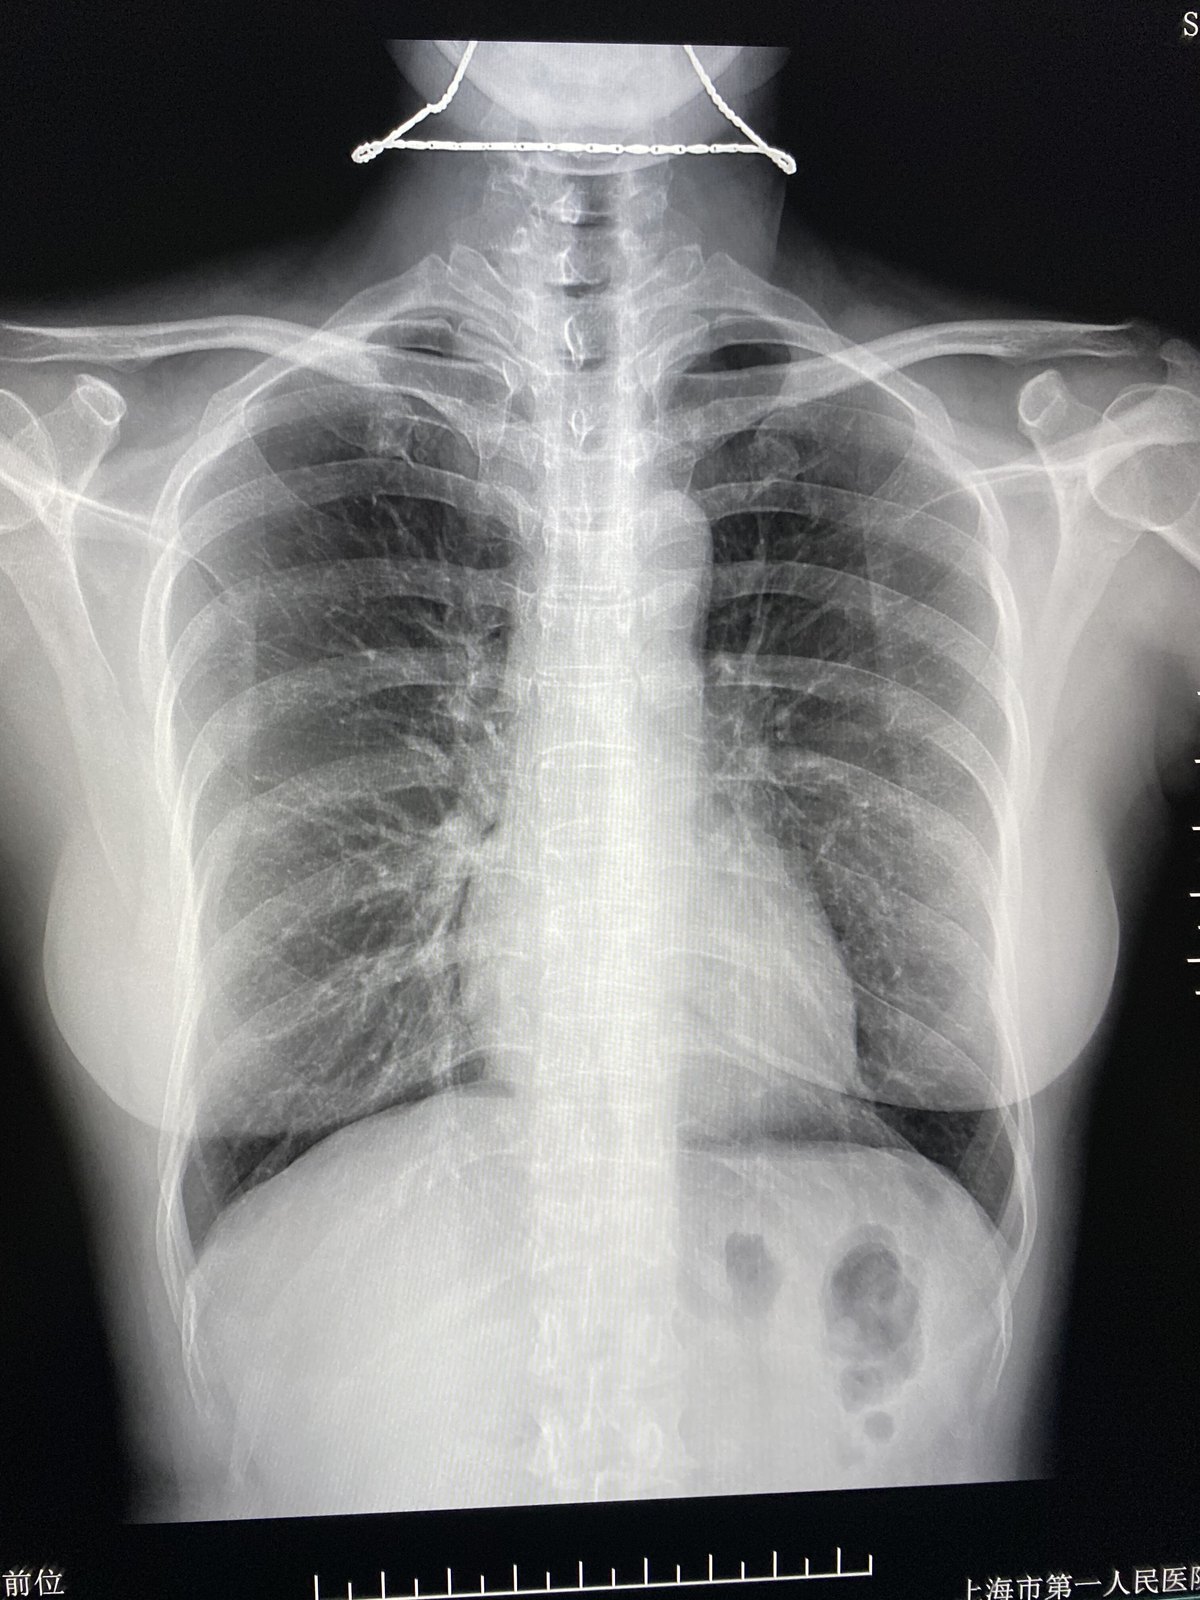

正常胸片健康

正常胸片健康,

04年得过肺结核,吃了一年的药,这是2个月前拍的胸片,医生说没事,可是

x线胸片可显示胸部软组织,以及骨骼,肺野,肺门,纹理,纵膈与横膈的影像

正常胸片

肺结节看胸片靠谱吗

【健康科普】拍个胸片,为什么要脱内衣?